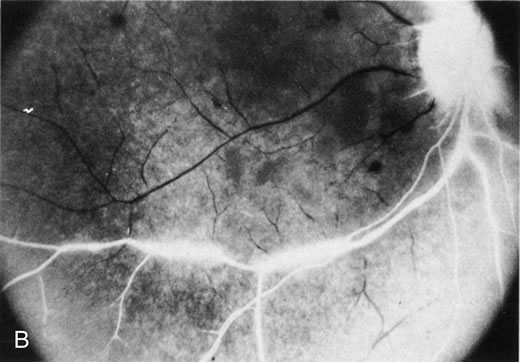

The finding of retinal vascular changes in patients with SLE correlates with the activity of the disease.214 The relationship of cotton-wool spots alone to CNS lupus has been debated, but to date no relationship has been established. Most experts feel that the finding of cotton-wool spots does not indicate the presence of CNS lupus. A much less frequent, severe retinal vasoocclusive disease has been described and does appear to be associated with CNS lupus, in particular, diffuse CNS dysfunction, such as an organic brain syndrome.214–223 This more severe retinal vasoocclusive disease may present as a central retinal artery occlusion, central retinal vein occlusion, branch artery occlusion, or most frequently, a diffuse retinal vasoocclusive process (Fig. 5), sometimes called retinal vasculitis. Although this last process sometimes has been called retinal vasculitis, the exact pathogenesis may not be true vasculitis. Cases of severe retinal vasoocclusive disease in SLE in association with the lupus anticoagulant also have been reported, and the retinal disease in these cases is presumed to be secondary to this autoantibody (Fig. 6).190,191 The prognosis for vision with this diffuse retinal vascular disease is poor and retinal neovascularization commonly develops. Panretinal photocoagulation may be of value in the treatment of the neovascularization of severe lupus retinopathy. Approximately 50% of eyes affected with this severe vaso-occlusive disease become blind. Although visual loss is common in those patients with severe retinal disease, in the more common mild retinopathy visual loss is unusual.223 Even less common than retinopathy is lupus choroidopathy, of which only a few cases have been reported to date.214,224–226 Early autopsy studies demonstrated the frequent presence of mononuclear inflammatory cells in the choroid of patients with untreated SLE.208 The clinical changes seen in patients with lupus choroidopathy include serous elevation of the retina, most often of the neurosensory retina, serous elevations of the retinal pigment epithelium, and combined elevations of both (Fig. 7). These clinical findings are associated with systemic vascular disease, either hypertension because of lupus nephritis or systemic vasculitis.226 Treatment of the underlying disease, with systemic corticosteroids and immunosuppressive agents if needed, and control of any hypertension can resolve these serous retinal detachments. Neuroophthalmic involvement in SLE includes cranial nerve palsies, lupus optic neuropathy, and central retrochiasmal disorders of vision.227–237 The central disorders include hallucinations and visual field loss.232,237 The optic nerve lesion most often seen in SLE is reported as retrobulbar optic neuritis. However, other optic nerve lesions can be seen, including anterior optic neuritis with optic disc edema, ischemic optic neuropathy, and a slowly progressive visual loss from lupus optic neuropathy.227–236 Autopsy studies have suggested that a microangiopathic process may be the pathogenesis of lupus optic neuropathy. Focal demyelination can be seen, but more severe lesions with axonal damage and even optic nerve infarcts have been demonstrated.227–229,231 One case demonstrated both demyelination and loss of axons with foci of total destruction of the optic nerve.229 This finding suggests that the same process may cause milder, reversible lesions and more severe irreversible infarct-like lesions. Transverse myelitis is seen in over 50% of patients with lupus optic neuropathy as compared with its overall frequency of 4% in patients with SLE.236 The frequency of clinical optic neuropathy in SLE patients has been estimated at 1% to 2% of patients with SLE.182–184 Scleritis occurs less commonly in patients with SLE. In one retrospective study of 97 patients with scleritis, 4% had SLE.56 Any type of scleritis may be seen, but anterior scleritis appears most commonly. Therapy that controls the underlying SLE typically controls the scleritis.2,56 |